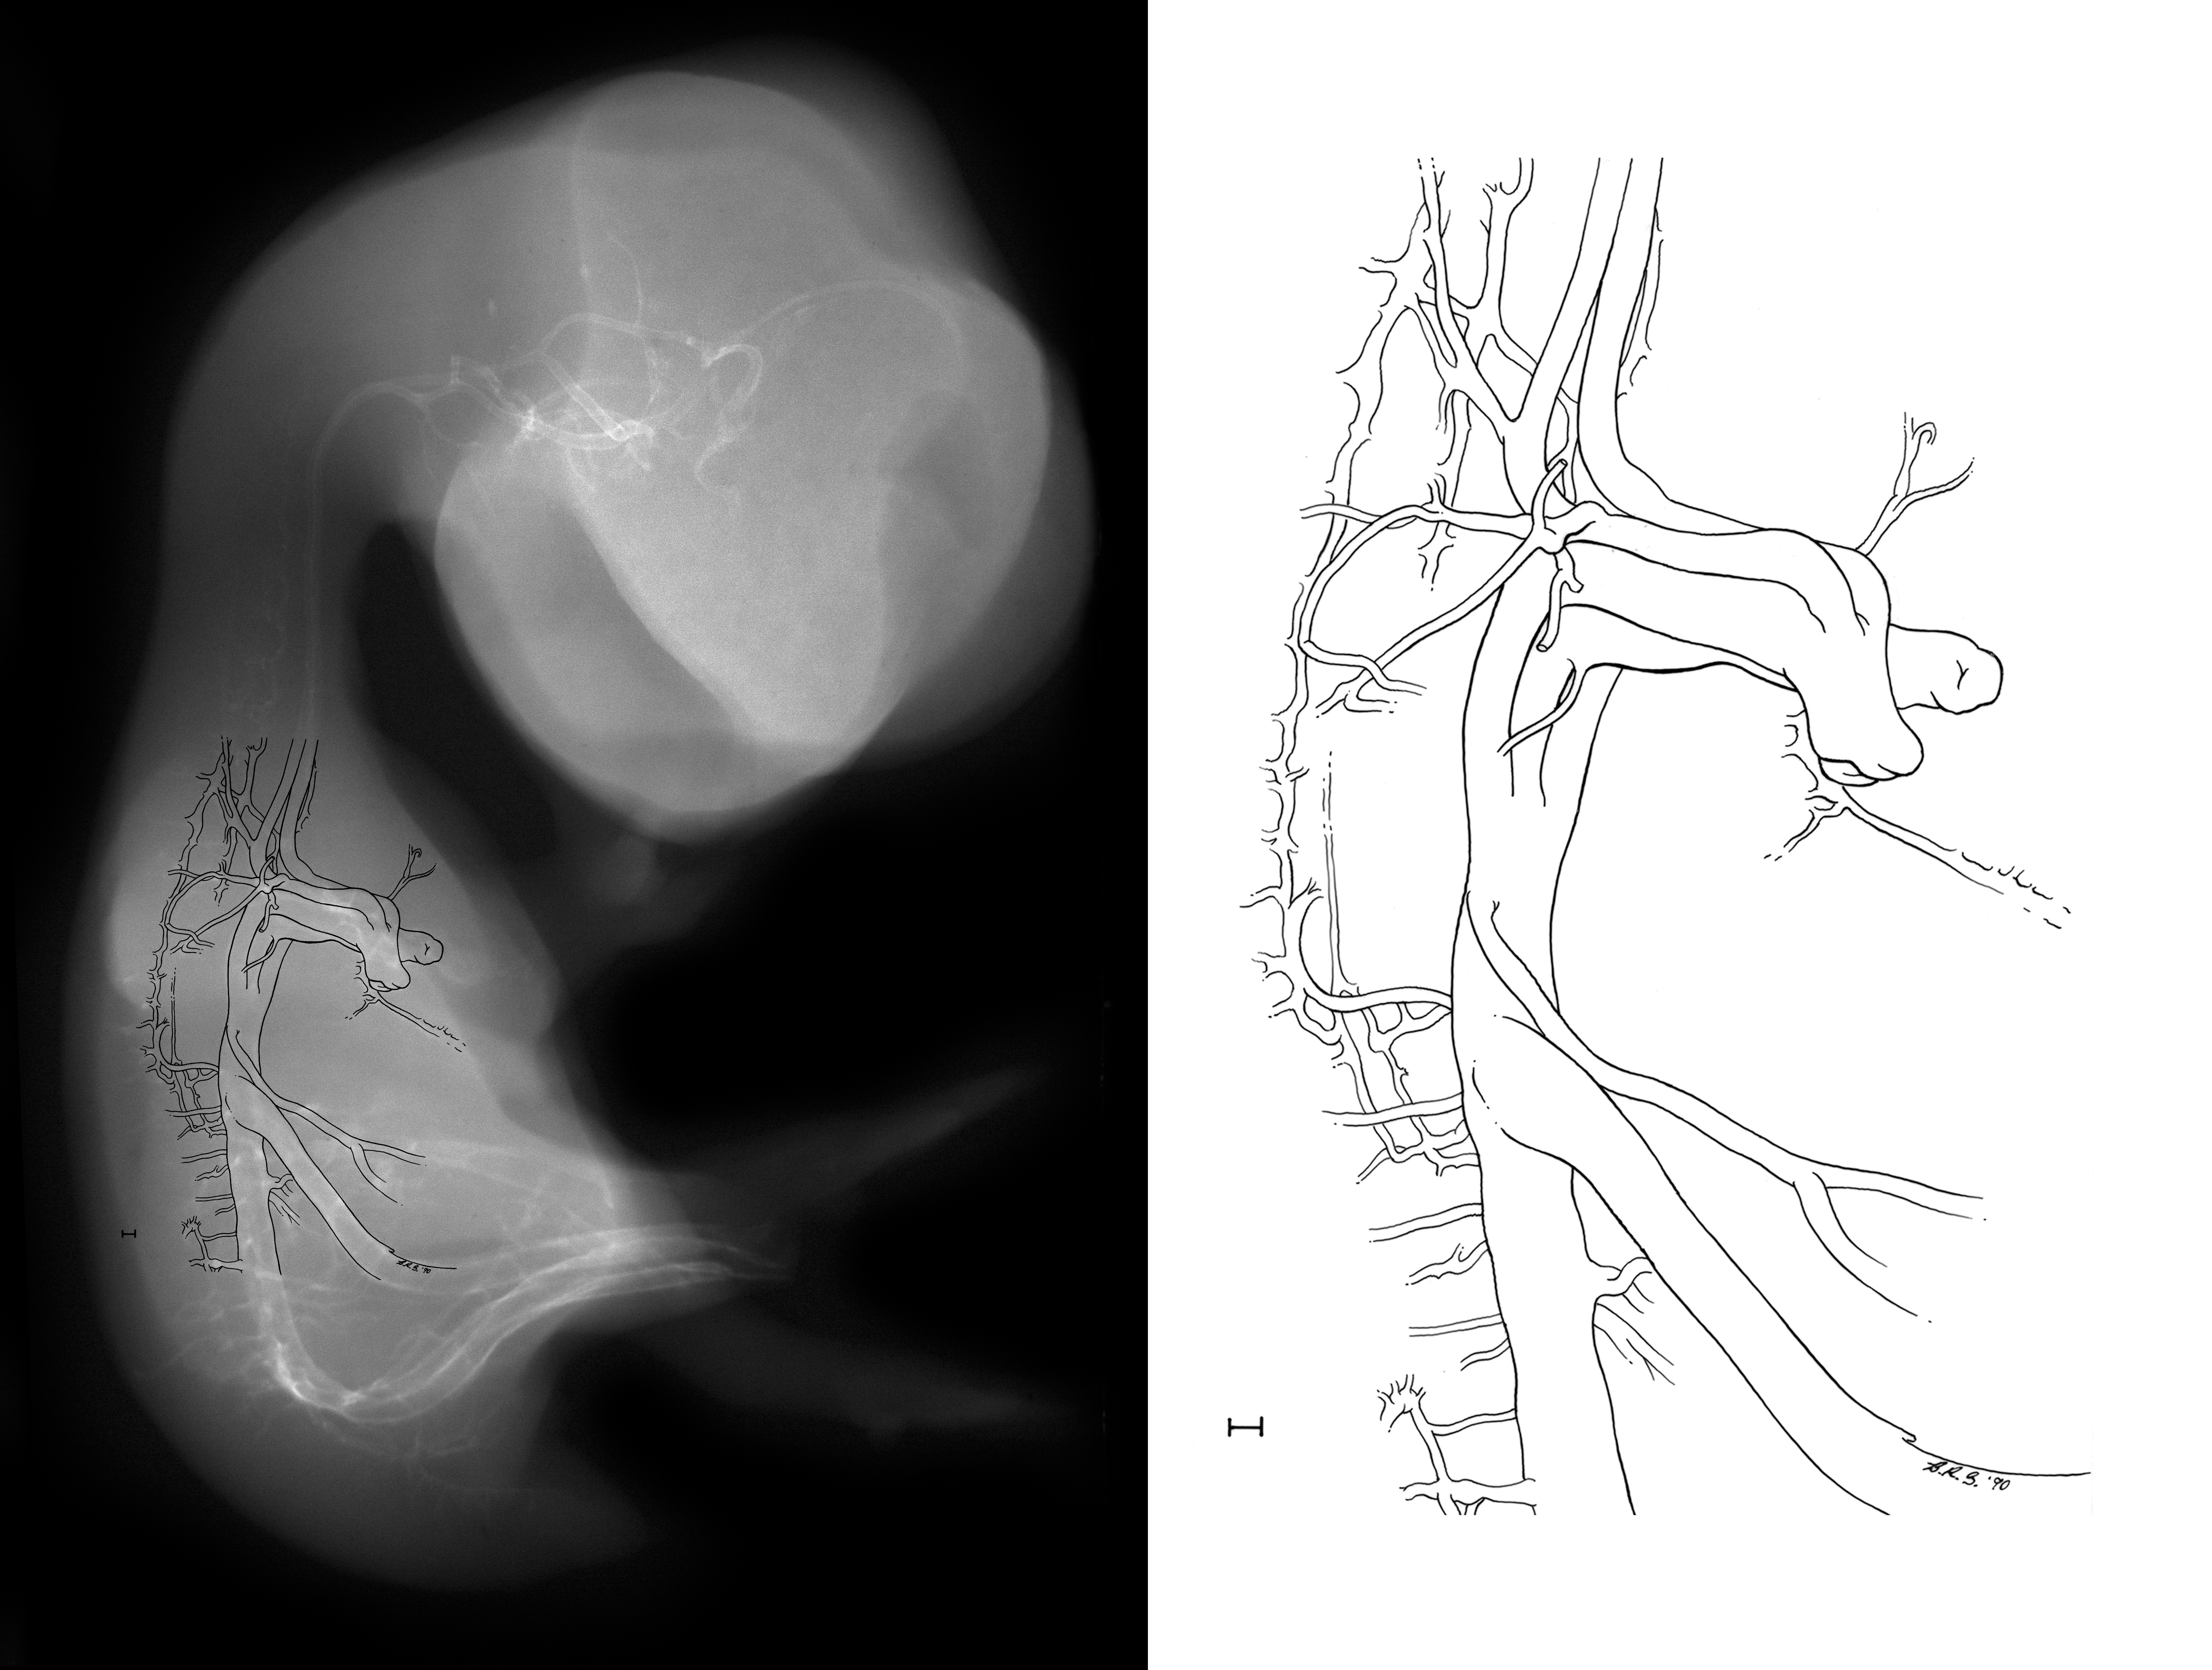

Chick Embryo Microangiography

Hamburger-Hamilton (HH) Stage 35 (approx. 8.5 - 9 days)

X-Ray Micrographs

Drawing